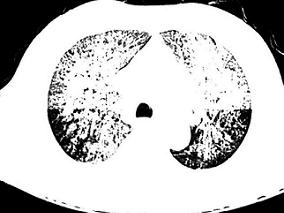

1小时条评论患者女性,42岁,2007年9月20日来诊。 一、主诉 反复发作性喘息20年,加重1周。 二、病史询问 (一)初步诊断思路及问诊目的 患者病史长达20年,初始起病时年纪较轻,20年来反复发作性喘息,诊断首先考虑支气管哮喘。问诊的目的应围绕着喘息症状的特点,如起病...